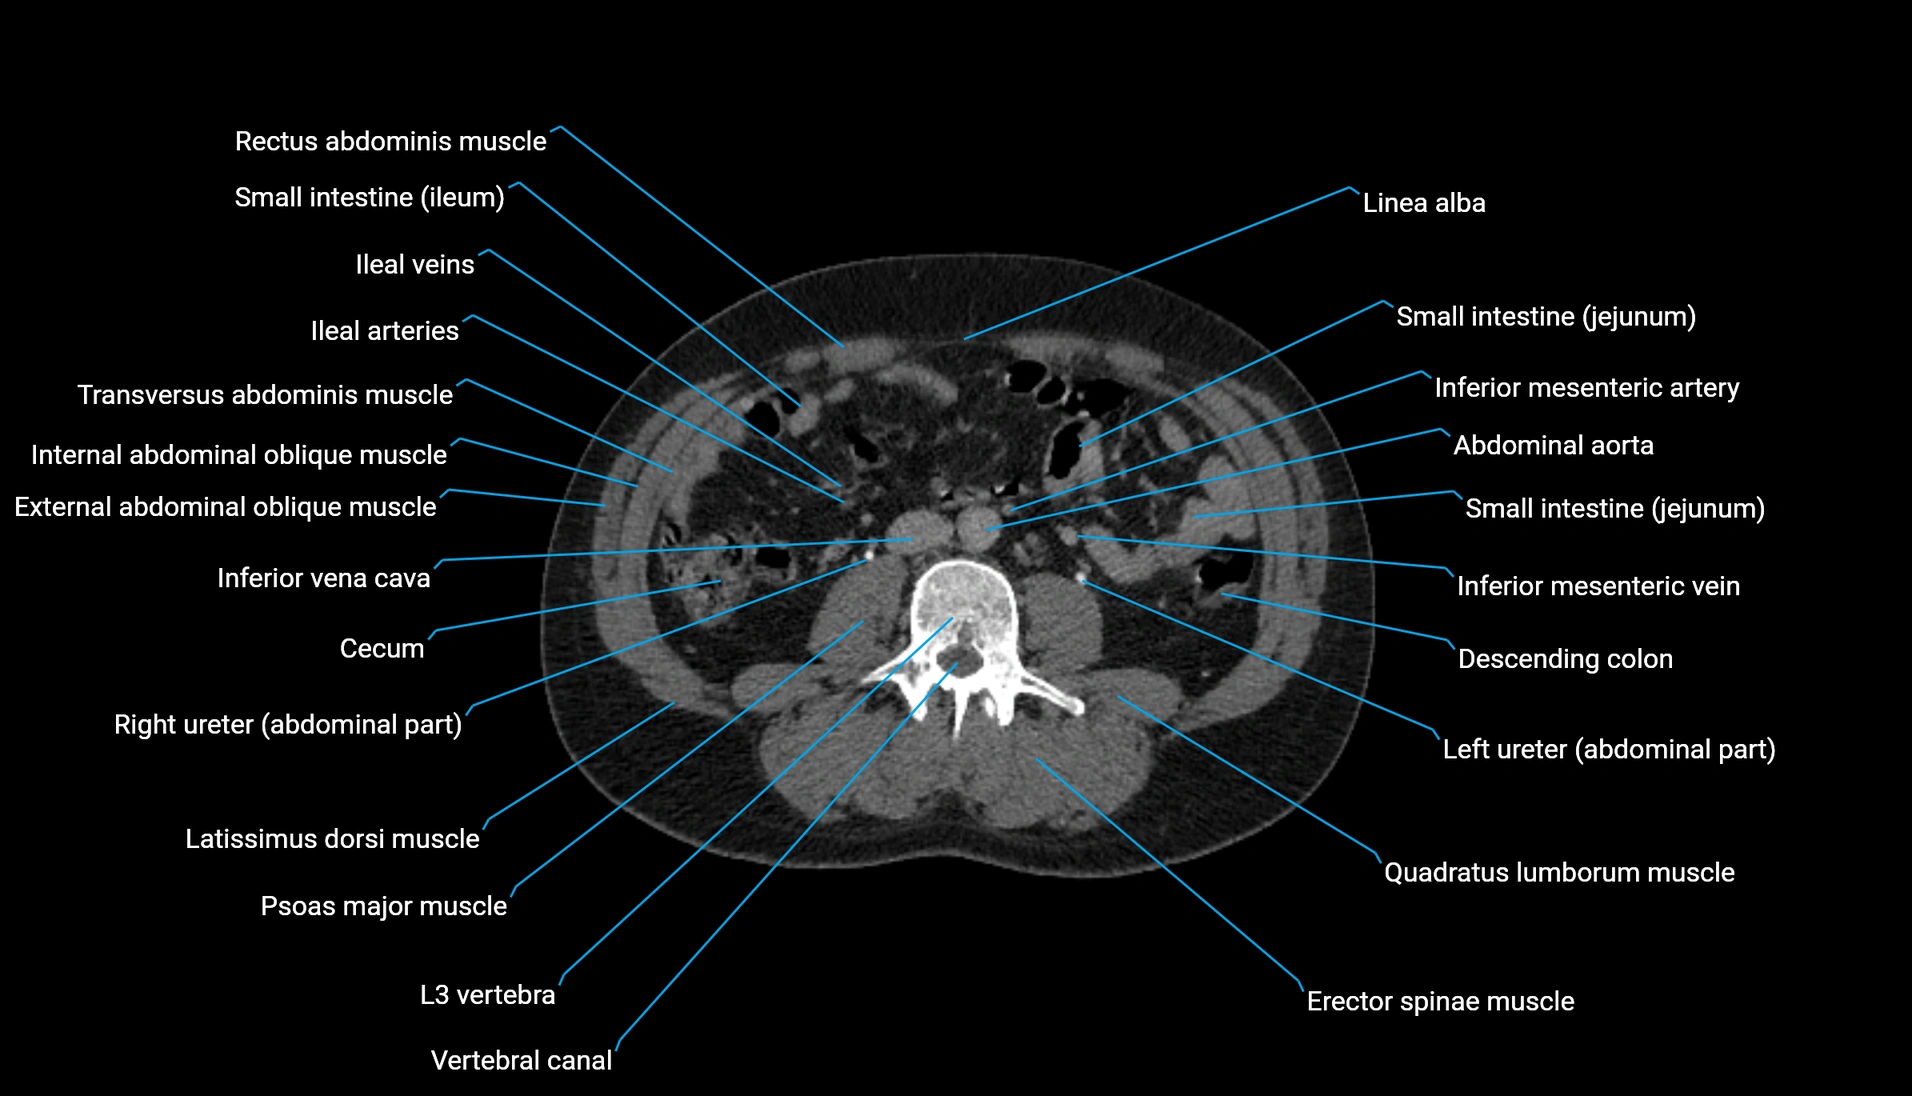

CT Appearance

Non-contrast CT:

-

Demonstrates cortical bone of acetabular rim in excellent detail

Detects fractures, dysplasia, retroversion, or bony overcoverage (pincer impingement)

3D reconstructions used in preoperative hip surgery planning

CT VRT 3D image

CT image